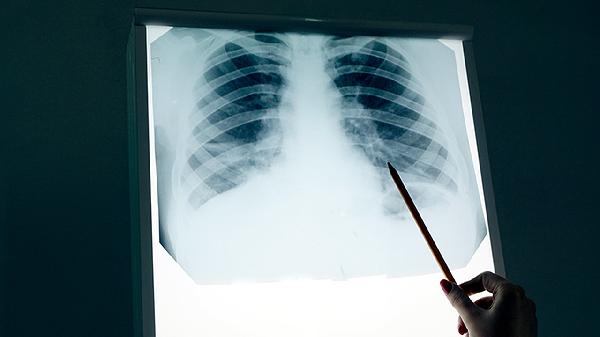

肺淋巴管肌瘤病是源于平滑肌细胞异常增生的弥漫性肺部疾病,属于低度恶性潜能肿瘤。疾病特征为双肺多发薄壁囊肿,可导致肺结构破坏。虽然疾病呈慢性进展性,但患者生存期差异较大,部分患者通过规范治疗可长期稳定。

早期可能仅表现为活动后气促,随着囊肿增多会出现反复自发性气胸。约40%患者会发生乳糜胸,伴随胸痛、咳嗽等症状。疾病进展期可能出现肺动脉高压和呼吸衰竭,此时需考虑氧疗支持。